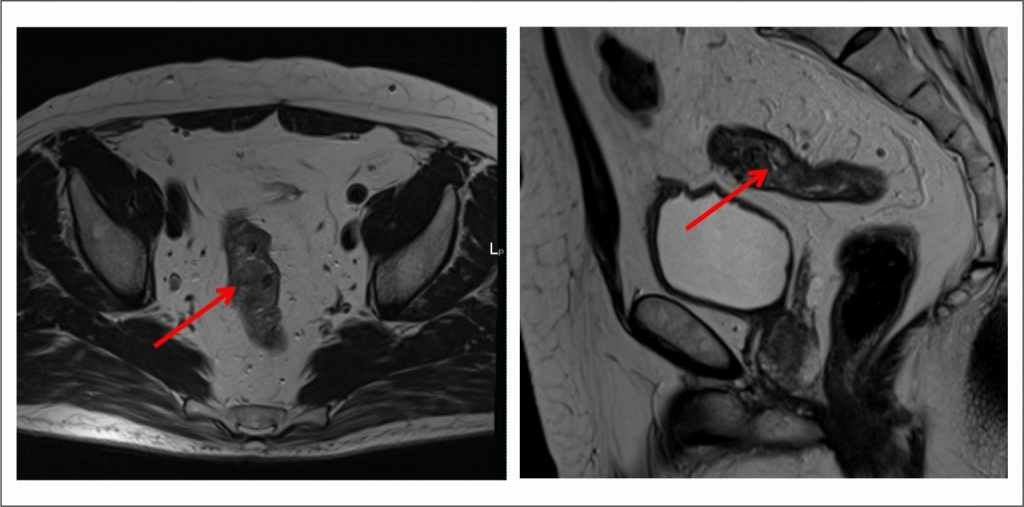

Как выглядит рак прямой кишки – фото

На фото рака прямой кишки можно заметить, что он значительно сужает просвет кишечника. Это является причиной запоров, переполненного живота, метеоризма.

На этом фото карцинома растет инфильтративно, охватывая стенку.

| МРТ-диагностика | Выявляет даже небольшие по размеру патологические очаги, метастазы и инвазию опухоли в соседние органы, ее топографическое положение относительно других структур. Метод безопасен, не создает радиационную нагрузку, в отличие от КТ. |